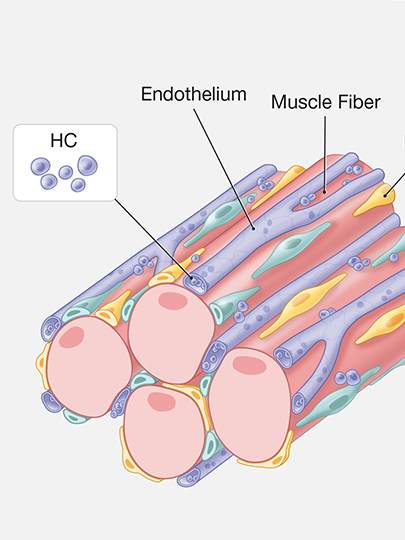

Running series of animated visual abstracts, Quick Takes, created for The New England Journal of Medicine as part of a team of illustrators, medical writers, and scientists. These short, iconographic animations aim to succinctly describe clinical trials and increase the awareness and understanding of important research findings.

Adopting The Journal’s visual style and asset library, I am responsible for the entire production process including narration editing, storyboarding, layout, illustration, and animation.